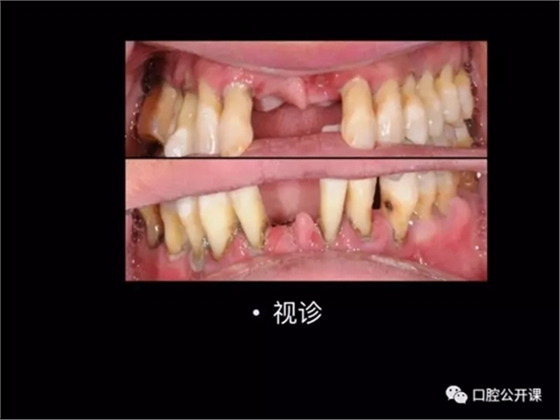

楊淑銀醫(yī)師用他的一例侵襲性牙周炎五年臨床病例追蹤來(lái)縮影一個(gè)青年牙周醫(yī)師的成長(zhǎng)之路,帶我們一起探索看似平凡枯燥的牙周基礎(chǔ)治療到底有怎樣的重要性?